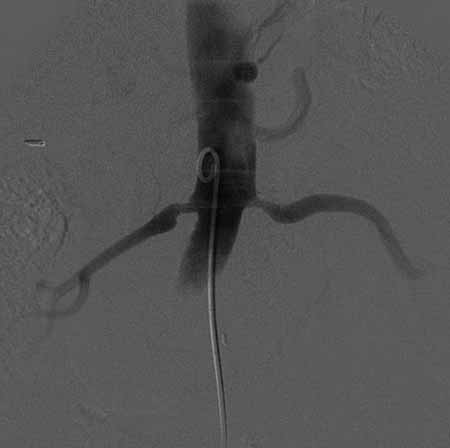

标题: DSA0088:肾动脉狭窄 [打印本页]

标题: DSA0088:肾动脉狭窄

女,63岁,高血压病史,160/100mmhg。

双侧肾动脉起始部狭窄,结合年龄考虑动脉粥样硬化所致.可进行球囊扩张或支架置入术.

双侧肾动脉起始部狭窄,该部位狭窄支架置入好象不可能,可球囊扩张或外科手术.